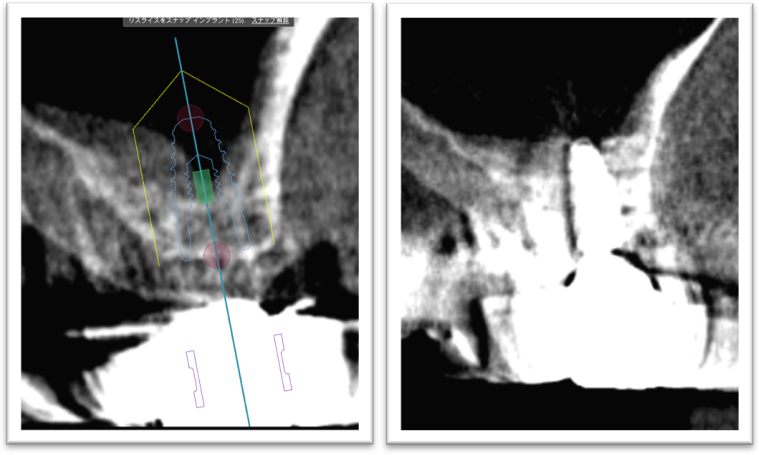

③ガイデッドサージェリーにてインプラント埋入しました。

④計画通りの埋入が出来ました。

レントゲン写真でも理想的な位置

に埋入できました。

術前ではインプラントを埋入する骨組織はほとんど有りませんが、

術後完全に骨内に埋入出来ました。